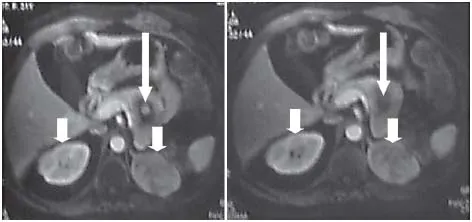

Androgen-producing tumors, mostly adrenal carcinomas, and a wide variety of ovarian tumors can present with symptoms/signs of virilization (clitoromegaly, deepening of the voice, frontal balding, and muscle hypertrophy), hyperandrogenism and chronic anovulation [7, 8] (fig. 1). Virilization seems to represent a distinctive feature for the presence of such tumors as it is extremely rare in women with PCOS, and when present it is usually mild. Adrenal carcinomas are large tumors that can hypersecrete testosterone or its precursors with or without concomitant cortisol hypersecretion. Ovarian neoplasms can be of variable size secreting mainly testosterone, although rarely can also co-secrete various androgen precursors [9]. Occasionally, ovarian neoplasms of epithelial origin may produce factors stimulating steroidogenesis in a paracrine fashion. Sertoli-Leydig cell tumor is the commonest virilizing ovarian tumor that occurs during the second to fourth decade of life and may be gonadotropin responsive [9]. A number of other tumors that also simulate the PCOS, such as hilus cell tumors, benign cystic teratomas and adrenal rest tumors have also been described; these tumors occur more frequently in postmenopausal women [8]. Ovarian hyperthecosis (nests of luteinizing cells distributed throughout the ovarian stroma) can present with a similar picture and be associated with severe IR [8]. The ovaries are enlarged and of an extremely firm texture as a result of extensive and dense fibroblast growth; the absence of follicle formation provides a clear morphologic distinction from the PCOS ovary [8]. The majority of virilizing tumors present during the middle age with symptoms such as rapidly progressive androgenic alopecia, deepening of the voice, increased libido and a male body habitus. However, particular attention should be paid to the rare cases of slowly evolving tumors, which can be clinically indistinguishable from PCOS [2, 7]. Although the majority of patients with tumors invariably have elevated androgen levels, only testosterone values >7 nmol/l (200 ng/dl) are highly suggestive of an androgen-secreting tumor [2, 7]. Occasionally, the documentation of an ovarian androgen-secreting tumor may be difficult as these tumors can be relatively small, eluding the detection with conventional imaging modalities [9]. Although in such cases bilateral adrenal and ovarian catheterization and sampling to document a gradient of an androgenic steroid has been employed, the detection rate remains relatively low [9]. Prompt diagnosis and management of these tumors are important, particularly in cases of adrenal carcinoma (fig. 2), as patients with localized disease exhibit a much more favorable prognosis compared to patients with more extensive disease [2].

Fig. 2. T1-weighted MRI of the abdomen demonstrating bilateral adrenocortical carcinomas (short white arrows) and a pancreatic neuroendocrine tumor (long white arrow) in a 34-year-old woman with multiple endocrine neoplasia syndrome type who was initially diagnosed to suffer from PCOS.